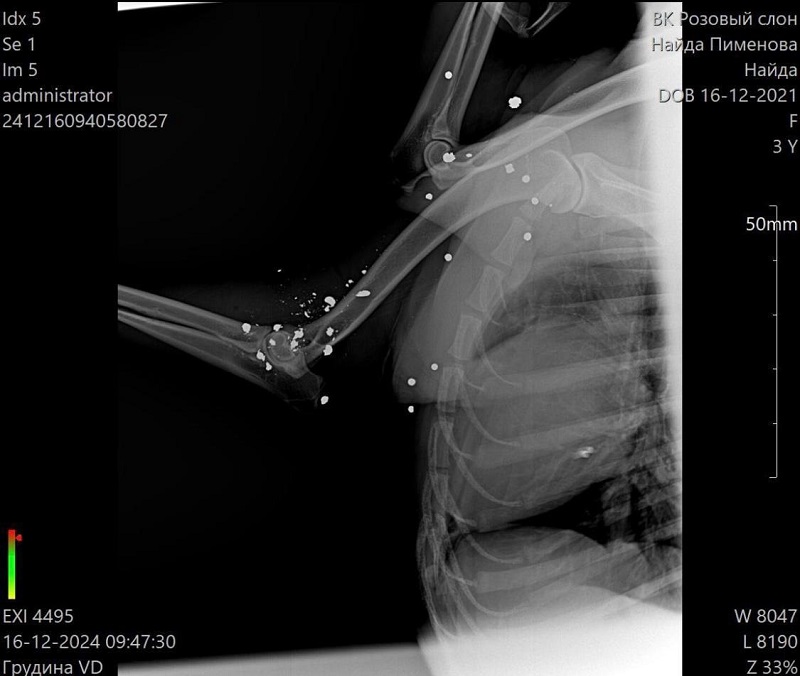

Получила продолжение история о собаке, которую неизвестный живодер буквально расстрелял на дороге в районе села Троекуровка. Несмотря на испытание, которая ей уготовила судьба, собака выжила, и те, кто сейчас занимается ее спасением, не опускают рук - борются за жизнь четвероногого друга. В Найду вошло более 30 пуль, одна из которых находится в очень опасном месте - в кармане сердца. И семье, выхаживающей несчастное животное, стоило усилий найти хирурга, который возьмется её оперировать. Однако, согласившийся ветеринар нашелся в Самаре, и на 9 января Найде назначена операция.